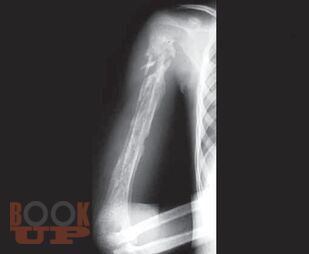

Thoroughly revised and updated with recent advances in the management of elective orthopedic conditions. Primer for orthopedic trauma has been included in annexures, enlisting commonly encountered fractures. Covers most of the questions asked in the postgraduate theoretical examinations. Difficult and advanced concepts are mentioned in points. Basic science in orthopedics has been discussed in detail. Sections are divided into body regions to establish correlation. New chapters added on Musculoskeletal Imaging, Preoperative Planning, Nanotechnology, Orthopedics in Digital Renaissance, Neglected Trauma to Bones and Joints (Annexure 4), expansion on Malunions, etc. Addition of lots of relevant figures and photographs along with tabulation. Various new diseases and techniques have been added. Enriched with more than 2200 relevant and beautiful illustrations.